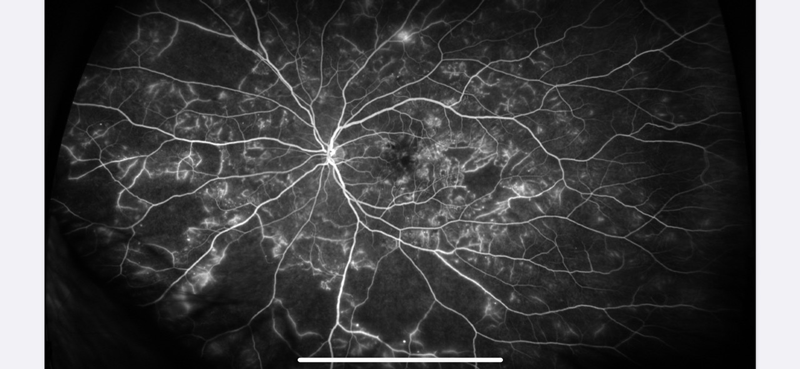

Angiografia retinal con contraste de fluoresceína: es un estudio que nos sirve para ver el estado de la vasculatura retiniana, muchas uveítis la pueden afectar.